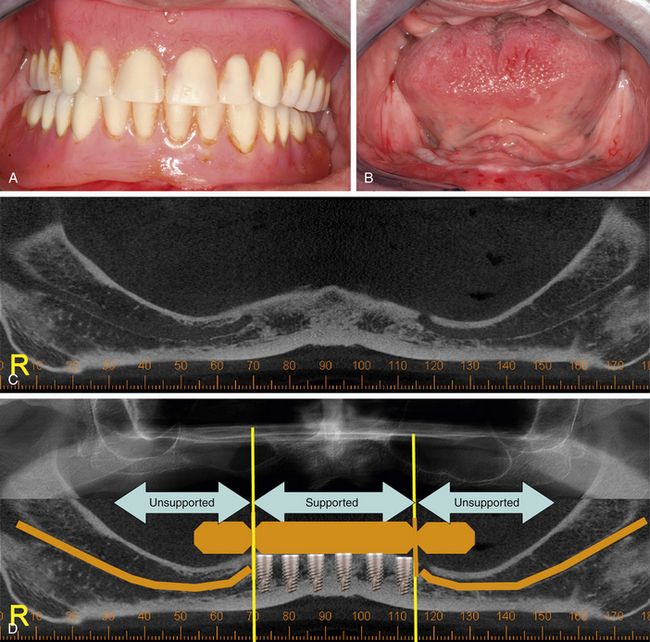

A, Completearch implantsupported fixed interim prostheses in centric Conventional Fixed Dental Prosthesis The bridge is held firmly in place by dental implants on each side of the missing tooth or teeth. This module will discuss the advantages and disadvantages of conventional fixed treatment options for replacing missing teeth and compare their published treatment outcomes and. It extends across an area that has no teeth and is typically made up of an. Previously. Conventional Fixed Dental Prosthesis.